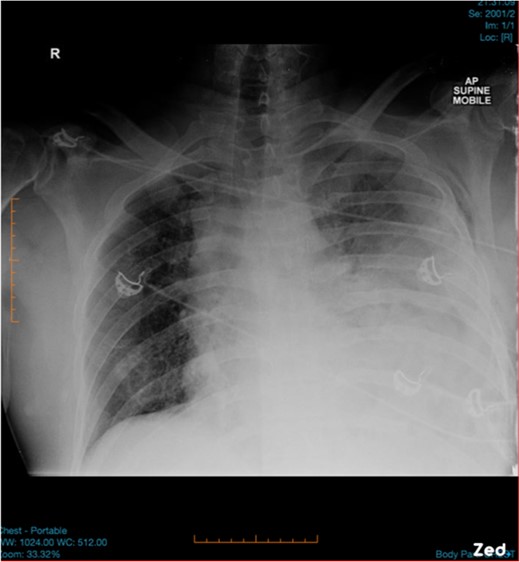

A 47-year-old male was brought to the Emergency department by ambulance after a high speed motor vehicle accident. On arrival, he had a Glasgow Coma Scale of 13, a patent airway with cervical spine collar in situ, spontaneous tachypnoeic breathing with an oxygen saturation of 97% on 15 l of oxygen. He had unequal breath sounds with decreased air entry on the left. He was tachycardic with a blood pressure of 110/70 mmHg. There were multiple bruises and abrasions to his torso and bilateral lower limbs. He had no previous medical history and was otherwise healthy. Initial chest x-ray was suspicious for a left-sided haemopneumothorax (Fig. 1) and an intercostal chest tube (ICCT) was inserted to the left side with a repeat x-ray confirming its position. However, there was minimal drain output and little swing. Subsequent computed tomography (CT) scan of the chest detected a left diaphragm rupture with a large diaphragmatic hernia where most of the left thorax was replaced by intra-abdominal contents (Fig. 2). A decision was made for emergency laparotomy to repair the diaphragmatic hernia. The patient was intubated in the emergency department prior to transfer to the operating theatre. While no ventilation problems were noted during transfer, the patient’s abdomen was seen to become progressively more distended to a point where it became tight and tympanic on percussion (Fig. 3). An underlying lung injury was suspected and the cardiothoracic team was called. At laparotomy, a significant pneumoperitoneum was confirmed with sudden escape of air upon entering the peritoneal cavity. The large hernia containing spleen, stomach and small bowel was reduced and the posterolateral diaphragmatic defect was repaired with a non-absorbable suture. This was followed by a left thoracotomy that identified a superficial laceration in the left upper lobe of the lung which was repaired with Prolene sutures and re-enforced with tissue glue. The patient was then transferred to the intensive care unit in a stable condition and made a good recovery. It is likely that the lung injury was caused secondary to intercostal catheter insertion during resuscitation in the Emergency Department. However, it could also have been secondary to associated left rib fractures or blunt trauma during the accident.

Initial chest x-ray was suspicious for left-sided haemopneumothorax.